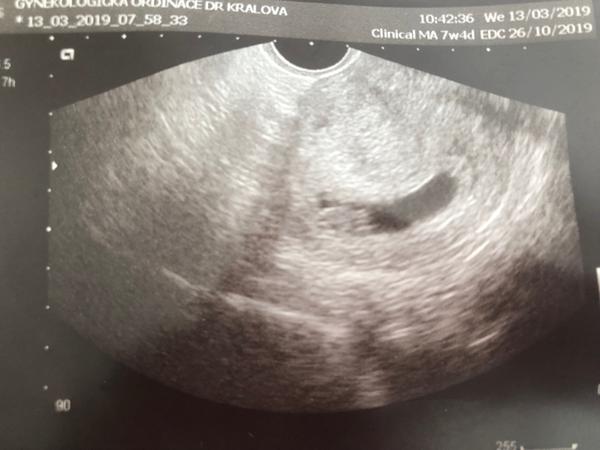

7tt podle MS u silnější maminky a špatně viditelný ultrazvuk

@petulinda29 tohle je 7+4 a uši a oči opravdu nevidím 😀 jen si moc dobre pamatuju kde mu buši srdíčko. Přestanete se zbytečně stresovat